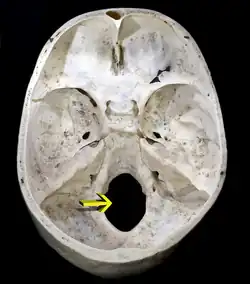

Otwór wielki[1][2], otwór potyliczny wielki[3], otwór potyliczny[4] (łac. foramen magnum, foramen occipitale magnum, foramen occipitale, formen cephalicum posterior) – nieparzysty otwór w czaszce niektórych kręgowców oraz puszce głowowej sześcionogów.

U ptaków i ssaków otwór wielki znajduje się w kości potylicznej pomiędzy łuską potyliczną (łac. squama occipitalis) u ssaków lub kością nadpotyliczną (łac. os supraoccipitale) u ptaków, która ogranicza go od tyłu, częścią podstawną (łac. pars basilaris ossis occipitalis), która znajduje się do przodu oraz częściami bocznymi (łac. partes laterales ossis occipitalis) leżącymi do boku od otworu. Otwór wielki łączy jamę czaszki z kanałem kręgowym[2][1][3].

U człowieka otwór wielki jest szeroko-owalny i zawiera:

- rdzeń przedłużony wraz z workiem oponowym

- tętnice kręgowe z żylnym splotem podstawnym

- tętnice rdzeniowe przednie i tylne

- gałęzie rdzeniowe nerwu dodatkowego (XI).

W procesie hominizacji doszło do przesunięcia otworu potylicznego ku przodowi czaszki - jest do przystosowanie do dwunożności, ponieważ umożliwia równomierne rozłożenie dużego ciężaru czaszki.